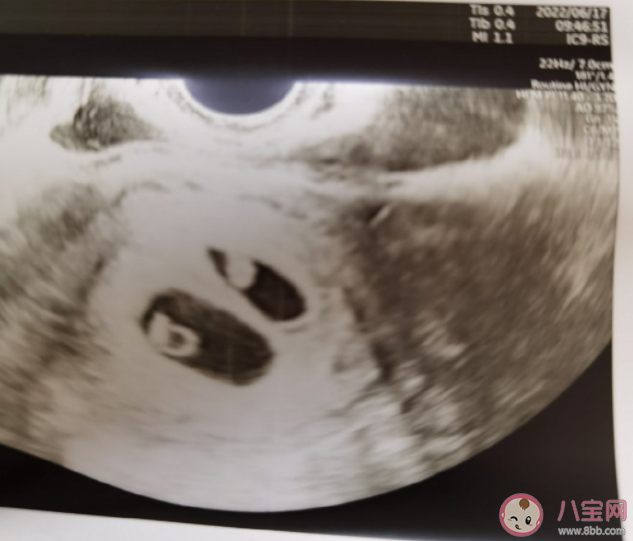

對于月經(jīng)正常的女性來講,停經(jīng)滿6周以后做B超多數(shù)都可以看到胚芽和心跳搏動,在這之前,沒有必要頻繁的抽血查hCG和孕酮水平,做B超。那么正常的胎心大概是多少?可以通過胎心心率判斷胎兒的性別嗎?下面八寶網(wǎng)小編帶來介紹。